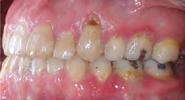

En la Figura 3 se muesta clase III molar y canina, el overjet y overbite negativos, en la Figura 4 las líneas medias coincidentes, la mordida abierta anterior, en la Figura 5 la clase III molar y canina, overjet y overbite negativos, en la figura 6 se ven formas de los arcos ovales, el apiñamiento severo superior e inferior.

En la radiografía lateral de cráneo tenemos (Figura 7) la clase III esquelética con un ANB de -1, hiperdivergencia, aumento de la altura facial inferior, proclinación de los incisivos superiores con 1 a plano palatino de 133°, línea roja sobre la longitud del incisivo superior.

En la radiografía panorámica (Figura 8) se observan 32 dientes presentes

en boca, con la rehabilitación de los órganos dentarios por oclusal, con obturaciones de amalgamas, e incrustaciones, y divergencias radiculares inadecuadas.

Figura 3. Lateral derecha. Figura 4. Frente intraoral. Figura 5. Lateral izquierda. Figura 6. Intraorales oclusales.

Figura 7. Radiografía lateral de cráneo. Figura 8. Radiografía panorámica.